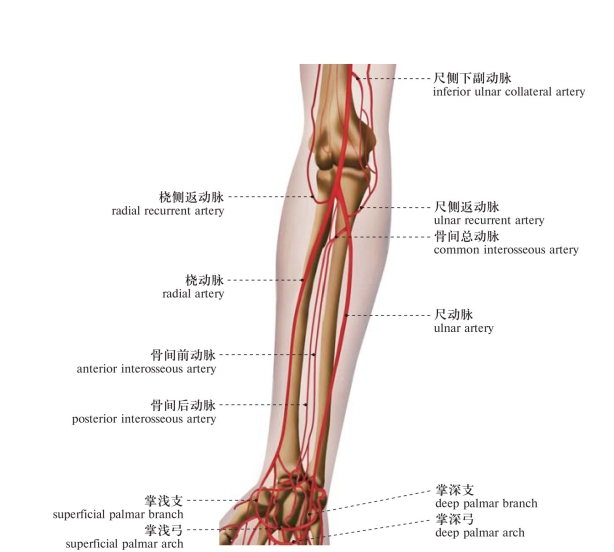

图392 肘及前臂的动脉

Arteries of the elbow and forearm